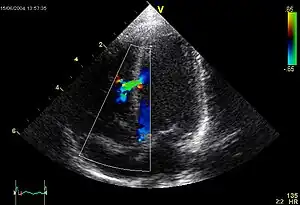

An abnormal echocardiogram: Image shows a midmuscular ventricular septal defect. The trace in the lower left shows the cardiac cycle and the red mark the time in the cardiac cycle when the image was captured. Colors are used to represent the velocity and direction of blood flow.

Echocardiography can help detect cardiomyopathies, such as hypertrophic cardiomyopathy, and dilated cardiomyopathy. The use of stress echocardiography may also help determine whether any chest pain or associated symptoms are related to heart disease. The biggest advantage of echocardiography is that it is not invasive (does not involve breaking the skin or entering body cavities) and has no known risks or side effects.[4] Not only can an echocardiogram create ultrasound images of heart structures, but it can also produce accurate assessment of the blood flowing through the heart by Doppler echocardiography, using pulsed- or continuous-wave Doppler ultrasound. This allows assessment of both normal and abnormal blood flow through the heart. Color Doppler, as well as spectral Doppler, is used to visualize any abnormal communications between the left and right sides of the heart, any leaking of blood through the valves (valvular regurgitation), and estimate how well the valves open (or do not open in the case of valvular stenosis). The Doppler technique can also be used for tissue motion and velocity measurement, by tissue Doppler echocardiography.